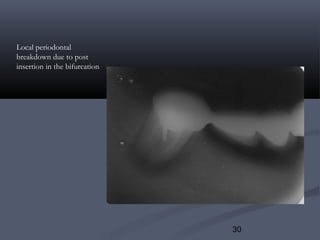

Local periodontal

breakdown due to post

insertion in the bifurcation

V. Tooth Perforation :V. Tooth Perforation :

May occur during pinhole ,post insertion or during root canal

treatments. It maybe occlusal to the periodontal ligament, in the. It maybe occlusal to the periodontal ligament, in the

bifurcation, or even in the pulp.bifurcation, or even in the pulp.

Treatment depends on accessibility ex if perforation is locatedTreatment depends on accessibility ex if perforation is located

occlusal to the periodontal ligament, preparation maybe extended toocclusal to the periodontal ligament, preparation maybe extended to

cover the defect.cover the defect.

Root canal therapy is indicated in case of perforations into the pulp.Root canal therapy is indicated in case of perforations into the pulp.

In other cases periodontal surgery maybe performed and aIn other cases periodontal surgery maybe performed and a

restoration is placed into the perforated area.restoration is placed into the perforated area.

Inaccessible areas such as bifurcations may necessitate extraction.Inaccessible areas such as bifurcations may necessitate extraction.